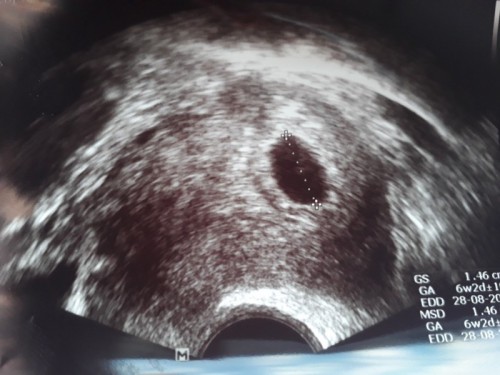

U/S ตอน 5W เจอแต่ถุงการตั้งครรภ์

นับจากประจำเดือนครั้งสุดท้ายก็5วีคแล้วค่ะ แล้วเราจะซาวเจอตัวน้องได้ตอนกี่วีคคะ หมอนัดอีก3อาทิต ให้ซาวใหม่ถ้ายังไม่เจอตัวน้อง หมอบอกว่าอาจจะเป็นท้องลม#ขอคำแนะนำหน่อยค่ะ #ขอบคุณสำหรับคำตอบค่ะ #ขอบคุณล่วงหน้านะคะ

ในใบซาวบอก 6w2d (ตอนไปซาวก็ไม่เจอตัวน้องค่ะ ) ถ้าหมอนัดอีก 3 อาทิตย์ ก็จะ 9w จะเจอตัวน้องค่ะ เราก็เจอชวง 9w แต่น้องก็ยังเล็กค่ะ😊